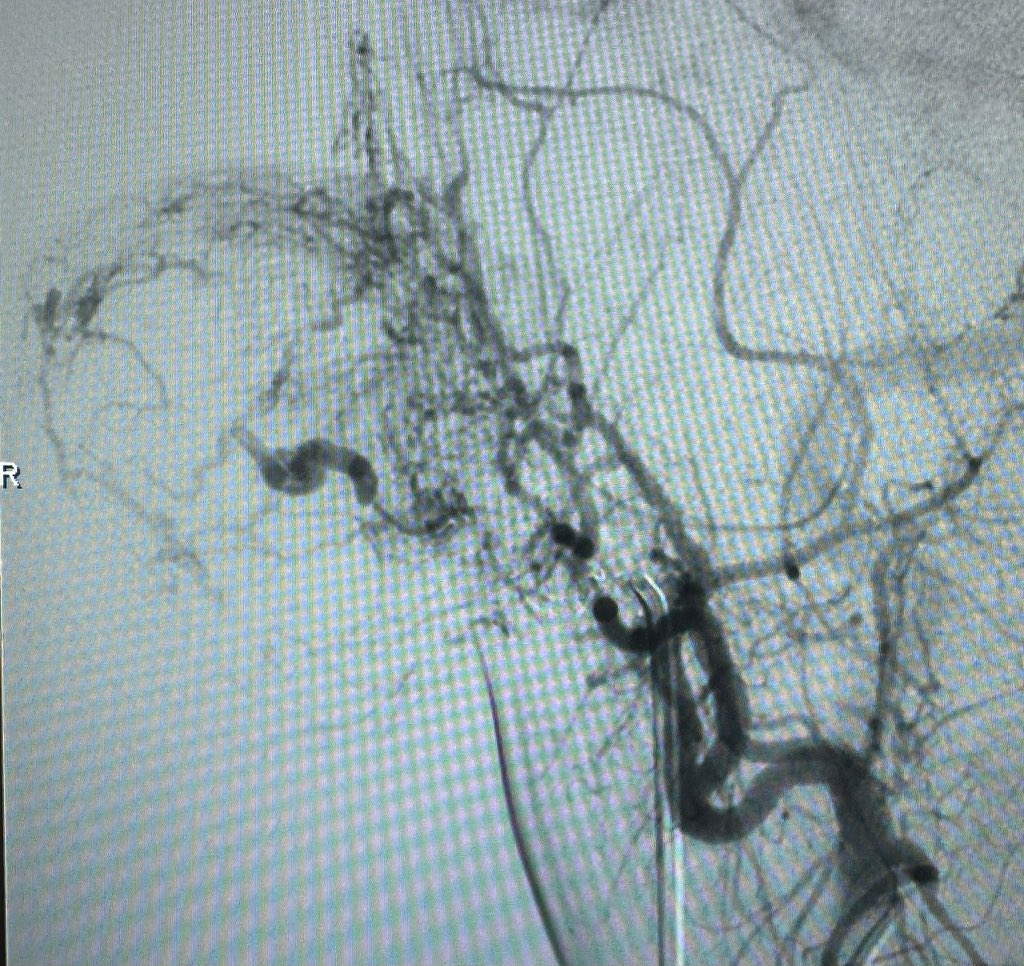

🚀 Advancing Neurointerventional Radiology at Muhimbili! 🇹🇿 This week, we welcomed Dr. Horikawa 🇯🇵 from the Dotter Institute 🇺🇸, collaborating on cutting-edge Neuro-IR cases, including embolization of an auricular vascular malformation. Pushing boundaries, improving lives!

🚀 Advancing Neurointerventional Radiology at Muhimbili! 🇹🇿

This week, we welcomed Dr. Horikawa 🇯🇵 from the Dotter Institute 🇺🇸, collaborating on cutting-edge Neuro-IR cases, including embolization of an auricular vascular malformation.

Pushing boundaries, improving lives!